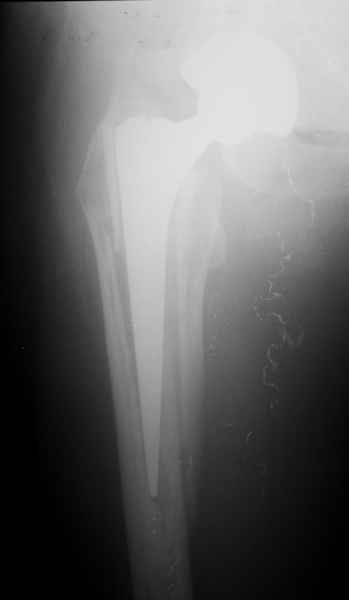

Пациента удалось осмотреть недавно. Достигнутый результат сохраняется. Перелом бедра сросся. Конечность опорная и безболезненная, ходит без трости. Ножка, похоже, реинтегрировалась, как и надеялись. Снимки и фото в приложении. Комментарии приветствуются.

Надо ли что-то делать дальше, как полагаете? Убрать винты? Убрать "удлинитель ножки"? Или оставить все, как есть? Спасибо заранее.